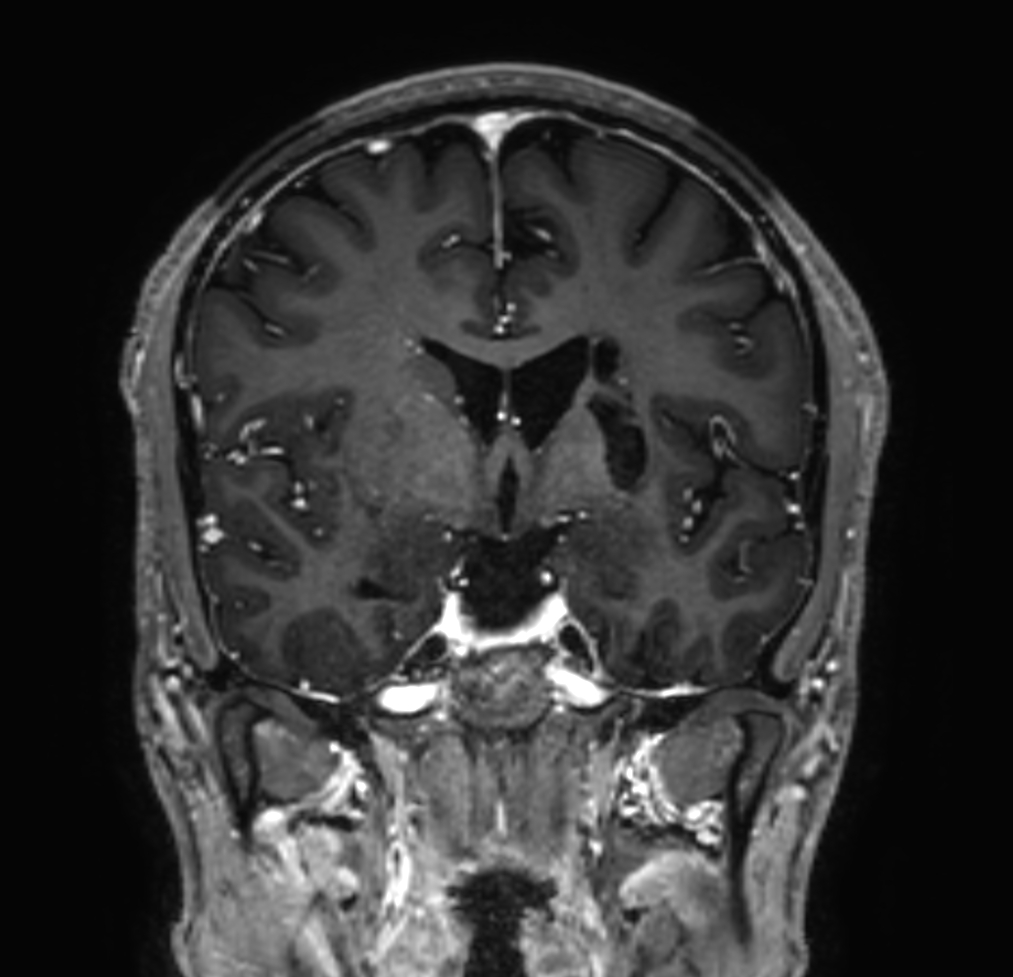

3D T1w TFE (post-gado)

-